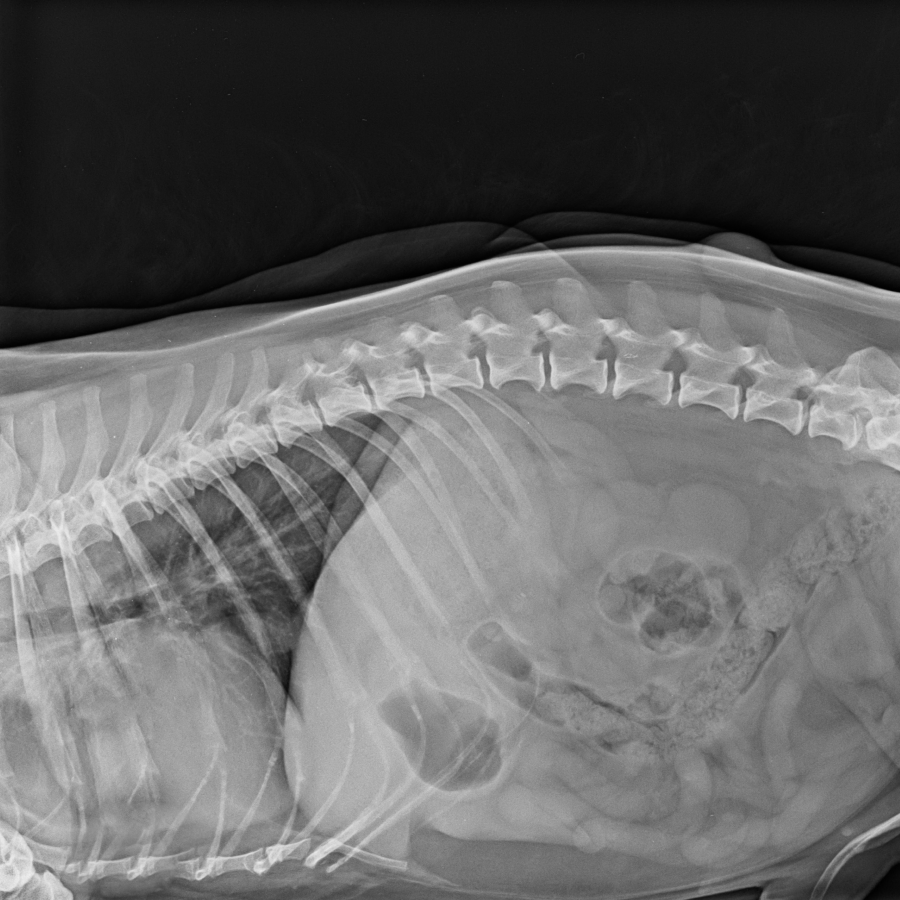

Además, el Instituto cuenta con un especialista en Traumatología y Ortopedia Infantil para atender estas dolencias de los pacientes desde el nacimiento hasta la adolescencia, un período especialmente importante ya que es el momento en el que el cuerpo se forma.

Son frecuentes las lesiones traumáticas y diferentes malformaciones o deformaciones.